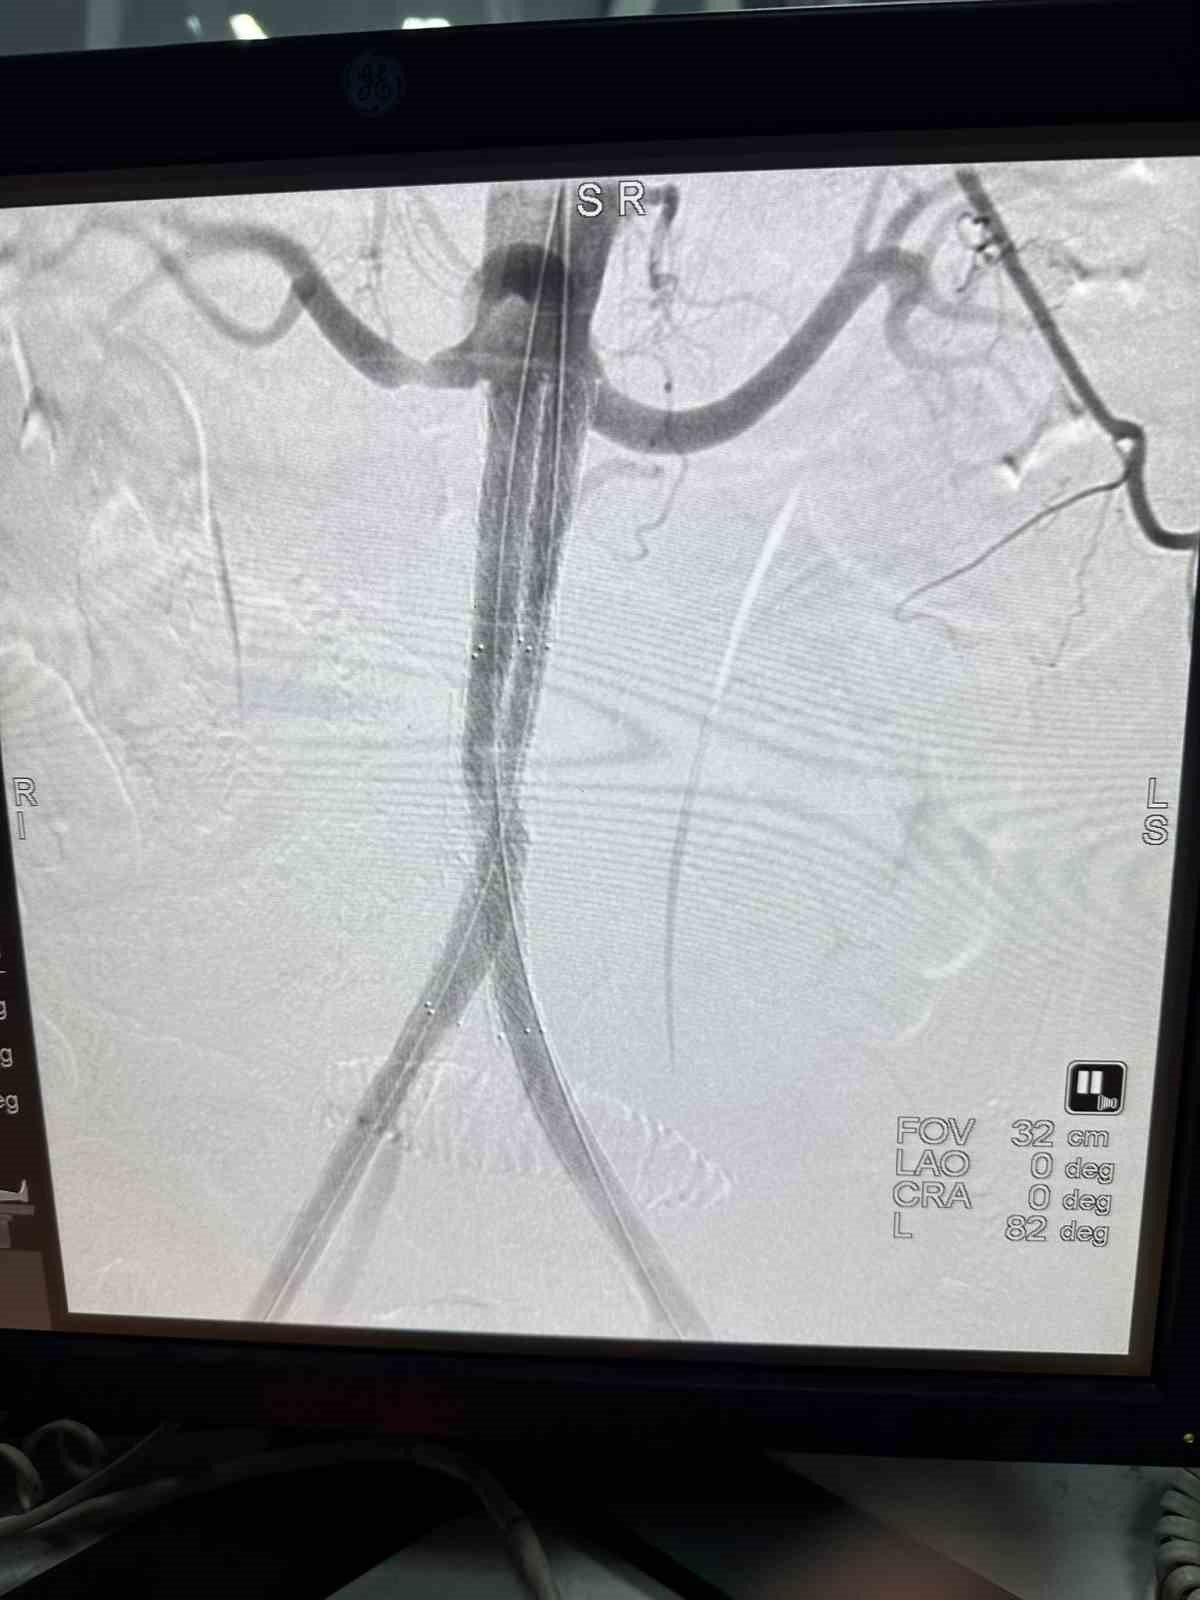

Hatay'da 63 yaşındaki bir hasta, ağrı, şişlik ve yürüme zorluğu gibi şikayetlerle hastaneye başvurdu. Yapılan tomografik damar film görüntülemesi sonucunda, hastanın iki bacağının kasık bölgesinden böbrek atar damar (renal arter) seviyesinin hemen altına kadar tıkalı olduğu tespit edildi. Uzm. Dr. Metin Onur Beyaz tarafından Leriche Sendromu teşhisi konularak hastanın tedavi altına alınması kararı verildi. Tedavi sürecinde Atlas Stent Greft ise teknolojisi kullanıldı. "Yapay damar" olarak bilinen Atlas Stent Greft, tıkalı damarların yeniden canlandırılmasını sağlamak için damar içine yerleştirildi. Sonrasında Stena Çok Katmanlı Periferik Akım Çevirici Stent uygulaması yapılarak işlem başarılı bir şekilde tamamlandı.

Stent greft veya diğer adıyla "yapay damar", damarın içine yerleştirilerek tıkalı bölgenin genişletilmesi ve normal kan akışının yeniden sağlanması amacıyla kullanılıyor.

INVAMED tarafından üretilen Atlas marka Stent Greft, damar içinde oluşan balonlaşmaları veya yaralanmaları tedavi etmek için özel olarak tasarlanmış bir tıbbi cihaz olarak ön plana çıkıyor. Bu cihaz, damarı destekleyerek doğru kan akışının yeniden sağlanmasına yardımcı oluyor.